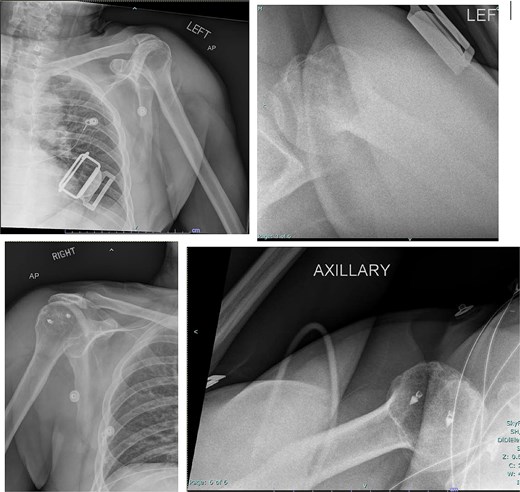

Both shoulders were reduced urgently by the orthopedic team, with immediate improvement in paresthesias (Fig. 2). Post-reduction CTs were significant for bilateral chronic rotator cuff disease with superior migration of the humeral heads, right-sided supraspinatus and subscapularis atrophy, and a left nondisplaced glenoid fracture (Figs 3 and 4). He was discharged home in bilateral slings.

Post-reduction CT of the left shoulder demonstrating superior humeral head migration relative to the glenoid.

Post-reduction CT of the right shoulder demonstrating superior humeral head migration relative to the glenoid, visualized evidence of prior rotator cuff repair surgery, and a nondisplaced anterior-inferior glenoid fracture.